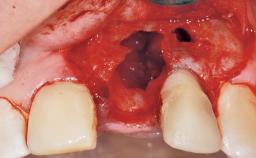

This 43-year-old male patient, a non-smoker, came to our practice because of a fracture of tooth 12 caused by a bicycle accident. Due to the combined para- and infrabony crown and root fracture, tooth extraction, and subsequent implant placement were suggested to the patient as the therapy of choice. The patient had high esthetic expectations with regard to the treatment outcome and asked for an immediate fixed provisional restoration. His individual esthetic risk profile summed up to a medium esthetic risk.

Socket Integrity Sufficient, with intact bone walls

Bone Volume Sufficient, with intact walls

Esthetic Risk Medium